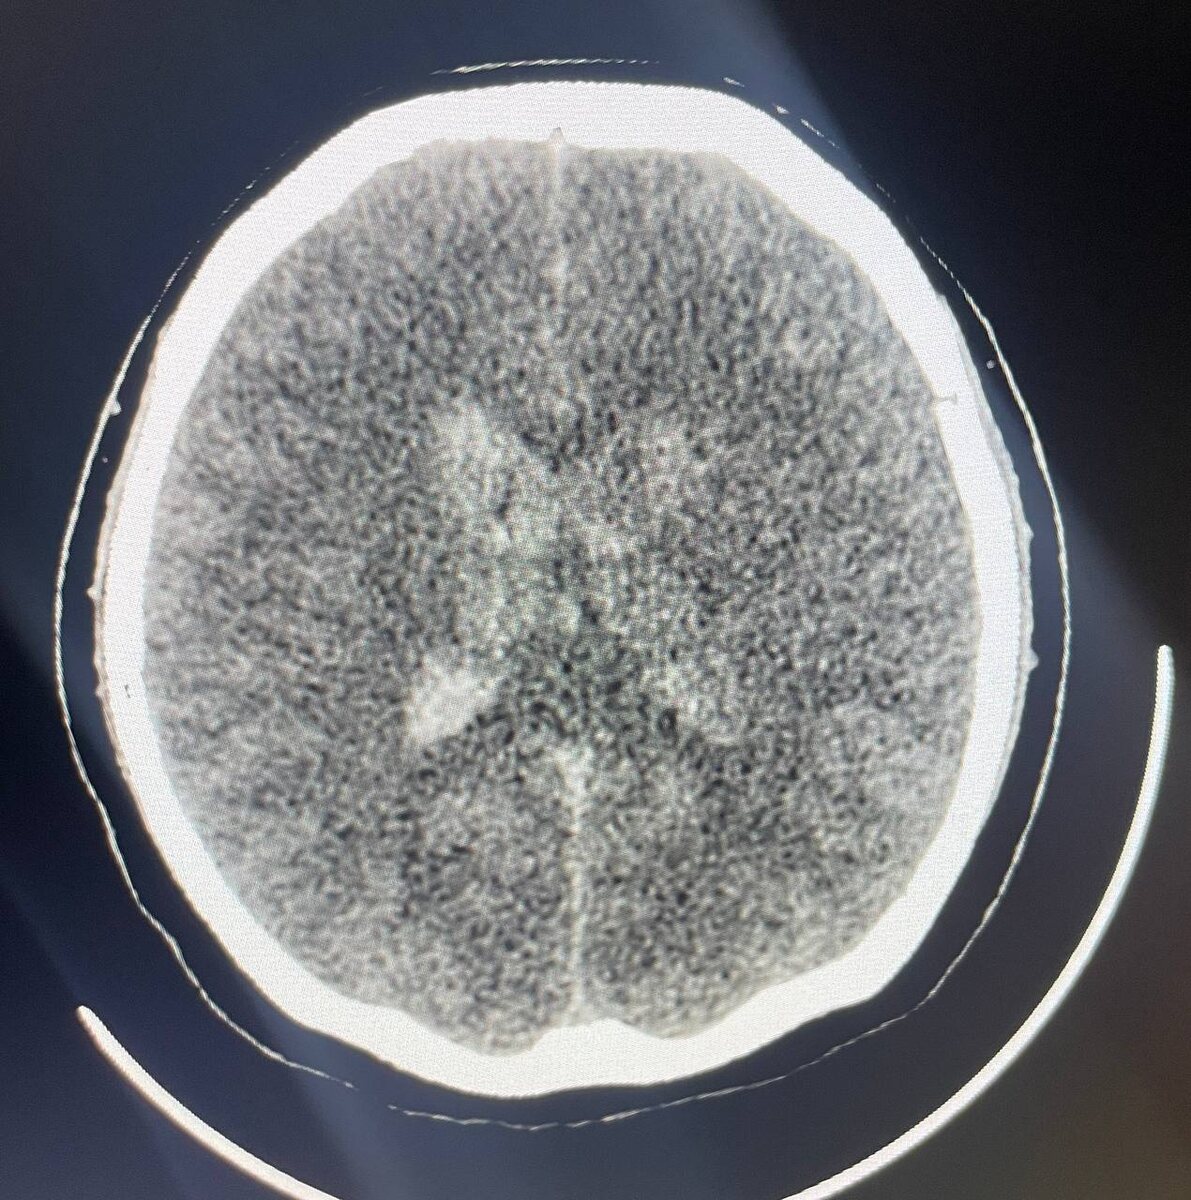

Если симптомом белого мозжечка нас не удивить, то подобное гиперденсное «свечение» базальных ядер и таламусов на фоне диффузного отёка головного мозга мне лично не встречалось, и в литературе ничего похожего не нашла. Объяснение этому явлению может быть тем же, что и при белом мозжечке: на фоне выраженного гипоксически-ишемического поражения головного мозга белое вещество выглядит очень темным, и на контрасте paradoxal dense sign ( самые уязвимые структуры- особенно бледные шары, таламусы и мозжечок) выглядят белыми. Иногда так выглядит и псевдосубарахноидальный знак - это как оптическая иллюзия. Попадались ли кому - нибудь подобные случаи? Интересную статью с поражениями базальных ядер и таламусов вследствие другого рода патологических изменений добавлю в комментарии. #белыебазыльныеядракт #белыеталамусыкт